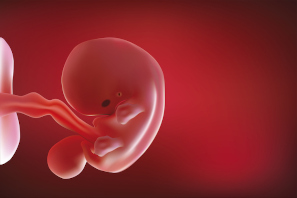

El bebé ha crecido de forma espectacular dentro del útero materno en la semana 8 de embarazo. Mide entre 10 y 14 milímetros. A partir de esta semana, para los médicos ha dejado de ser un embrión y ha "ascendido" de categoría de feto, y así será hasta el final del embarazo.

"Mientras que en el periodo embrionario se desencadena la formación de los órganos y tejidos, en el periodo fetal estos ya están completamente configurados y se produce su crecimiento y maduración. La justificación del cambio de nombre es que el embrión se desarrolla de forma gradual hacia una forma humana identificable".

- La cabeza del niño es muy grande en proporción al resto del cuerpo y siempre está inclinada sobre el cuerpo.

- Los rasgos faciales que se habían empezado a esbozar, van perfilándose.

- Los ojos que se habían situado a los lados -como un pez-, se van acercando entre sí, aunque aún se encuentran a bastante distancia, alrededor de 160º.

Sus brazos y piernas se han alargado y las palas, que se convertirán en manos y pies, se van separando del resto del cuerpo y aparecen en ellas unas hendiduras que dejan entrever lo que serán sus dedos.